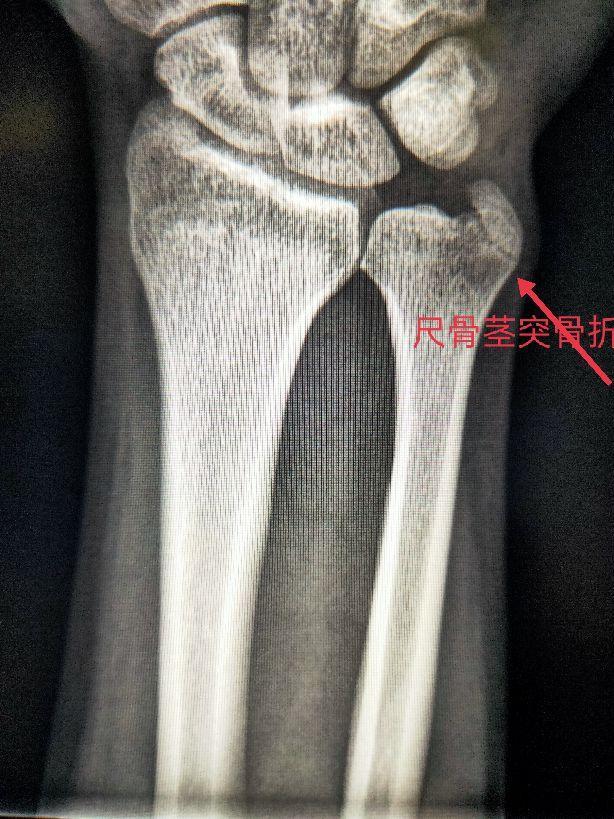

尺骨为前臂的稳定骨,是两根前臂骨中位于内侧且较长的骨,分二端一体。尺骨上端膨大,其上突的鹰嘴呈不整的四方形。它与肱骨滑车下缘相对应,构成肱尺关节。尺骨下端的是尺骨小头和尺骨茎突。尺骨小头与桡骨的尺骨切迹相对应,构成桡尺远侧关节。

四、尺、桡骨骨折X线片

尺骨桡骨骨折以桡骨远端骨折多见。其次是尺骨桡骨双骨折,多发生于青少年。